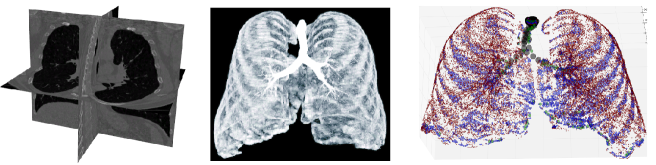

Refer to caption

Fig. 1: The preprocessing to transform the input image (left) into a probability image (center) and then into graph format (right). Nodes in the graph are shown in scale (as different colours) to capture the variations in their local radius.

The image data is preprocessed to convert it into a graph format. First, the 3D CT image data is converted into a probability map using a trained voxel classifier according to (Lo et al., 2010). This step converts intensity per voxel into a probability of that voxel belonging to the airway lumen. These probability images are transformed to a sparse representation using a simple multi-scale blob detector. Next, we perform Bayesian smoothing, with process and measurement models that model individual branches in an airway tree, using the method of (Selvan et al., 2017). This three-step pre-processing procedure yields a graph output of the input image data, as illustrated in Figure 1. Each node in this graph is associated with a 7limit-from77-dimensional Gaussian density comprising of spatial location 𝐱p=[x,y,z]subscript𝐱𝑝𝑥𝑦𝑧{\mathbf{x}}_{p}=[x,y,z] in the image, local radius (r𝑟r), and orientation (vx,vy,vz)subscript𝑣𝑥subscript𝑣𝑦subscript𝑣𝑧(v_{x},v_{y},v_{z}), such that 𝐱i=[𝐱μi,𝐱σ2i]subscript𝐱𝑖subscriptsuperscript𝐱𝑖𝜇subscriptsuperscript𝐱𝑖superscript𝜎2{\mathbf{x}}_{i}=[{\mathbf{x}}^{i}_{\mu},{\mathbf{x}}^{i}_{\sigma^{2}}], comprising mean, 𝐱μi7×1subscriptsuperscript𝐱𝑖𝜇superscript71{\mathbf{x}}^{i}_{\mu}\in{\mathbb{R}}^{7\times 1}, and variance for each feature, 𝐱σ2i7×1subscriptsuperscript𝐱𝑖superscript𝜎2superscript71{\mathbf{x}}^{i}_{\sigma^{2}}\in{\mathbb{R}}^{7\times 1}. The node features are normalized to be in the range [1,1]11[-1,1] for each scan to make all features of equal importance at input and to help in training the models.

The nodes in a graph that represent an airway tree are expected to have a certain behaviour. Nodes along a branch of airway will have a parent node and a sibling node. If the node is either a terminal node of an airway then it only has a parent node. In cases of bifurcations or trifurcations, the most neighbours a node can be connected to is three or four respectively. Taking this behaviour into account we allow for a larger number of possible neighbourhood of 101010. To obtain an initial connectivity, 𝐀insubscript𝐀in{\mathbf{A}}_{\text{in}}, we connect nodes to their 10 nearest neighbours based on spatial distance. These over-connected graphs, with node features 𝐱i14×1subscript𝐱𝑖superscript141{\mathbf{x}}_{i}\in{\mathbb{R}}^{14\times 1}, are the input graphs for both models. Figure 3 (left) visualises an over-connected input graph.